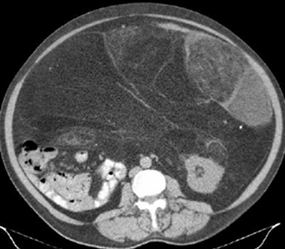

Fig 171. Liposarcoma.

TAC axial. Gran masa con densidad de grasa que ocupa gran porcentaje de la cavidad peritoneal. Presenta algunos septos gruesos y áreas heterogéneas, por liposarcoma.